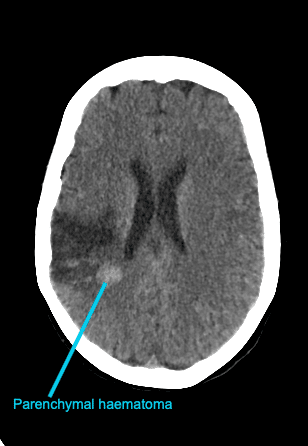

Bonus image

This is a CT scan of a different patient it demonstrates the appearance of a parenchymal haematoma following an MCA ischaemic stroke.

- Parenchymal haematoma (secondary haematoma)

Conversely, parenchymal haematomas are far more concerning. They are larger and can cause sudden clinical deterioration due to significant mass effect. Haematomas usually appear a few days after the infarct onset. They appear as hyperdense haematomas within infarcted hypodense brain parenchyma.